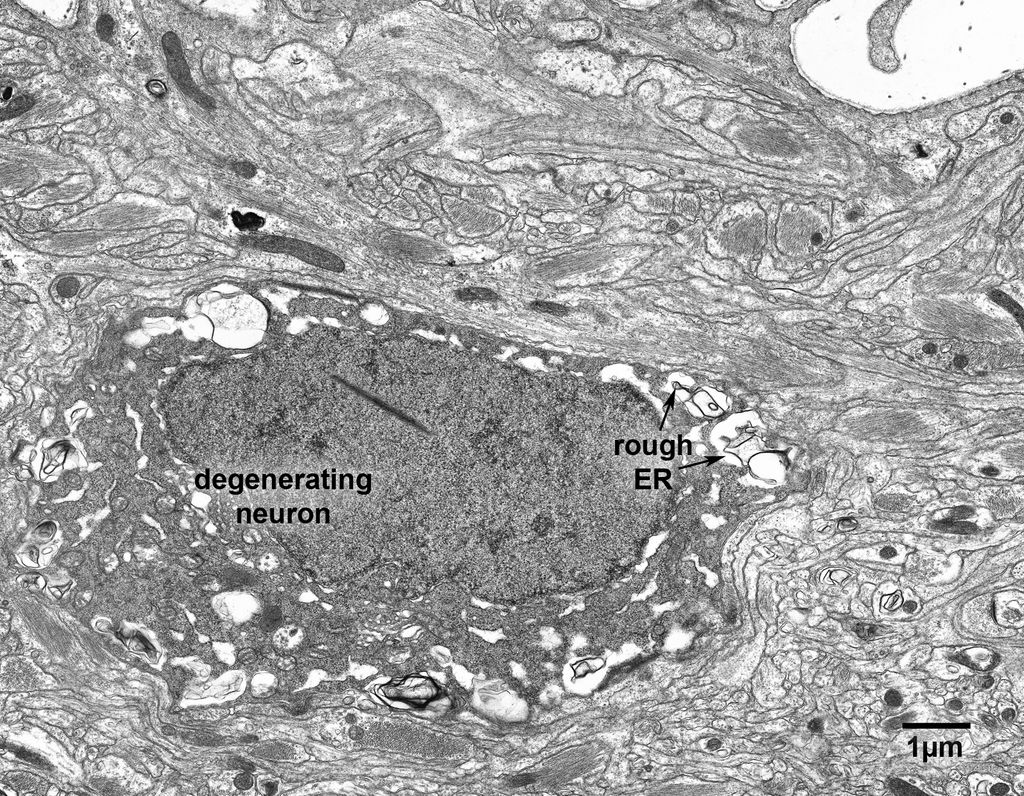

Figure 16.1

Fig. 16.1. A degenerating neuron in layer 1 of area 46 in a 25 year old monkey. It is not common to encounter degenerating neurons , since there is no significant loss of neurons with age. The cytoplasm and nucleus of this neuron have become electron dense, and the cisternae of rough endoplasmic reticulum and the nuclear envelope are distended.